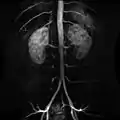

Contrast enhanced MRA of the abdominal aorta demonstrating normal paired arteries.

Contrast enhanced MRA of the abdominal aorta demonstrating normal paired arteries. The celiac artery and its branches; the stomach has been raised and the peritoneum removed.